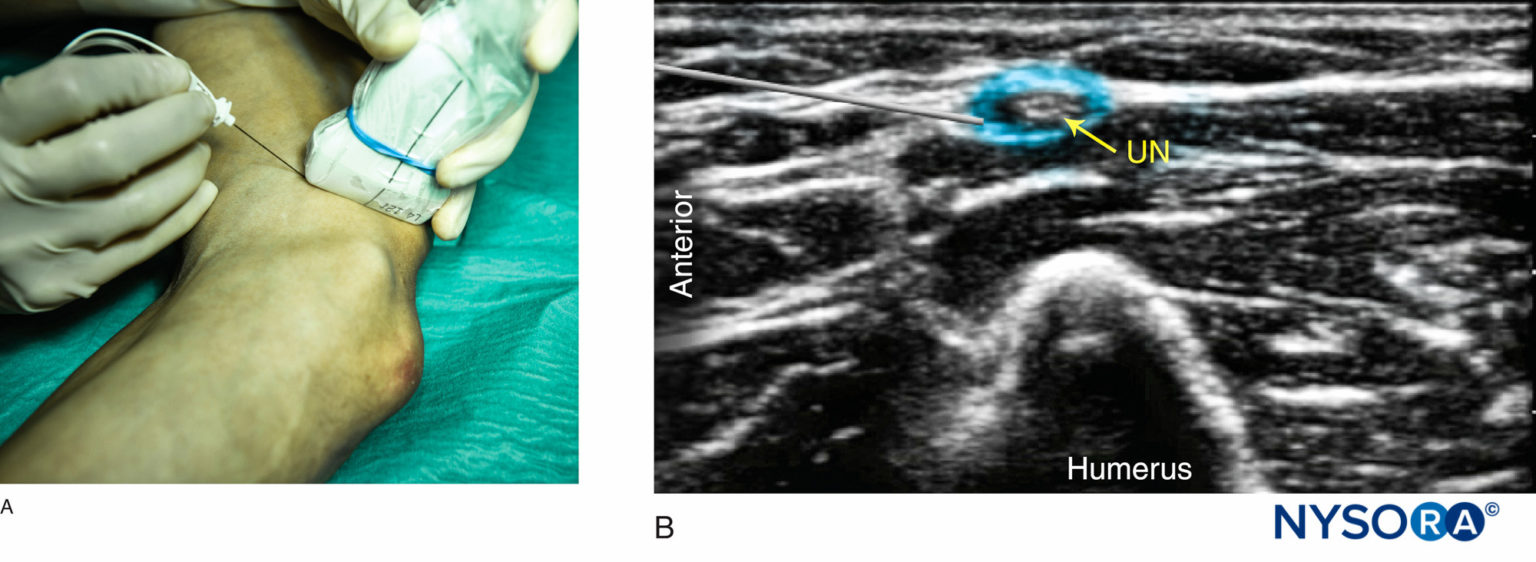

From www.nysora.com

UltrasoundGuided Blocks at the Elbow NYSORA Ulnar Nerve Block Ultrasound 7 additionally, analgesia can be achieved without local infiltration which distorts the wound, thereby enabling easier skin closure and a more aesthetically pleasing result. While the retroepicondylar groove and its surrounding structures are quite superficial, the use of ultrasound (us) imaging. Transverse at wrist crease or distal third of the forearm (figure 1) goal: The median nerve is commonly found. Ulnar Nerve Block Ultrasound.

UltrasoundGuided Blocks at the Elbow NYSORA Ulnar Nerve Block Ultrasound Local anesthetic injection next to the median and ulnar nerves and the sensory branch of the radial nerve. Transverse at wrist crease or distal third of the forearm (figure 1) goal: 7 additionally, analgesia can be achieved without local infiltration which distorts the wound, thereby enabling easier skin closure and a more aesthetically pleasing result. While the retroepicondylar groove and. Ulnar Nerve Block Ultrasound.

UltrasoundGuided Blocks at the Elbow NYSORA NYSORA Ulnar Nerve Block Ultrasound 7 additionally, analgesia can be achieved without local infiltration which distorts the wound, thereby enabling easier skin closure and a more aesthetically pleasing result. While the retroepicondylar groove and its surrounding structures are quite superficial, the use of ultrasound (us) imaging. The musculocutaneous nerve often branches off more proximally and may be located in a plane between the biceps and. Ulnar Nerve Block Ultrasound.